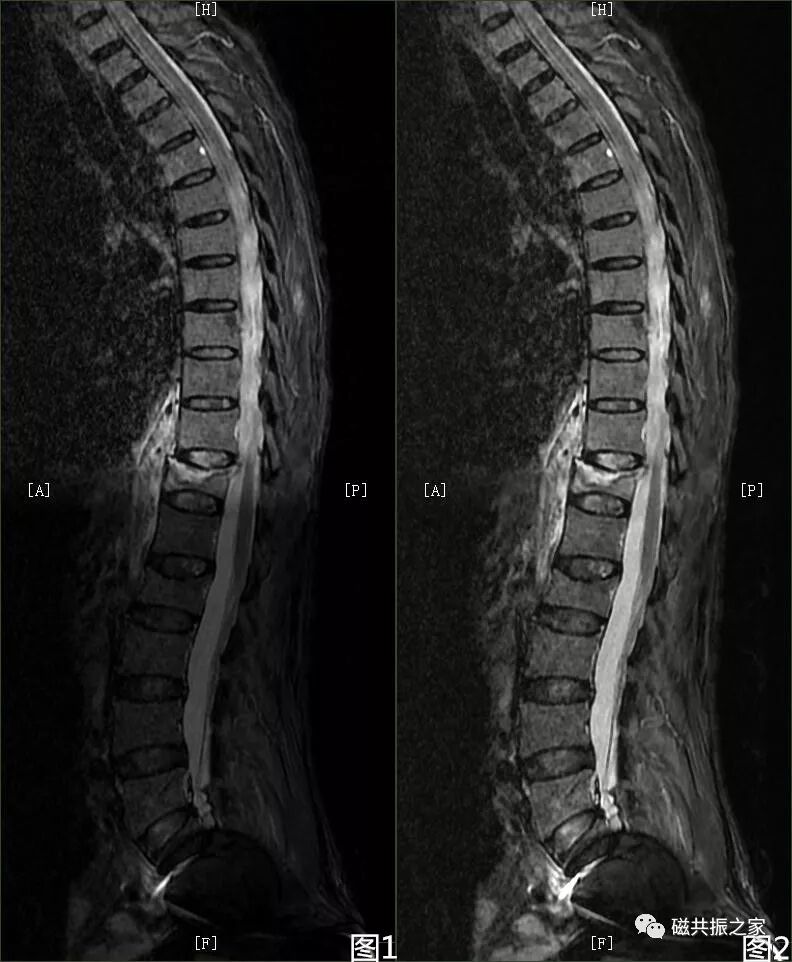

此外,还有其他容易识别的伪影。骨科金属植入物在高场强时会引起更广泛伪影,表现为低信号强度和脊髓变形。外周信号伪影因线圈单元与扫描范围不匹配产生,有多种表现形式。拼接伪影在脊柱扫描拼接中,因金属异物、参数不一致等因素,导致上下两段对比度不一致。同时,阅片时还需注意不要忽略正常解剖结构,如椎基静脉孔和神经血管脂肪簇等。